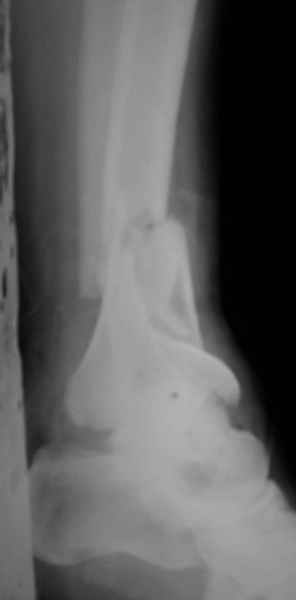

Открытый оскольчатый перелом н/3 голени.

Здравствуйте, коллеги! 16/10/06 г. В отделение поступила больная с производственной травмой - Открытый оскольчатый перелом метафиза и метадиафиза обеих костей правой голени со смещением отлоков.

Здравствуйте коллеги! В данной ситуации я полностью согласен с мнением Александра Николаевича! Практически любой внутрисуставной(тем более приведенный на снимках) перелом требует открытой репозиции.Судя по приведенным рентгенограммам, в области дистального тибио-фибулярного сочленения имеется "минус" ткань на tibia, которая может потребовать костной пластики.Метод фиксации любой,главное ранние движения в суставе. С уважением Руслан Ш.

К слову, тема этого обсуждения обозначена неточно, тут перелом дистального суставного конца типа 43-C, а не "открытый оскольчатый перелом н/3 голени", т.е. диафизарный, 42-.

Действительно, речь идет о сложном внутрисуставном, да еще и открытом переломе 43С.3.

1. Представленные рентгенограммы во-превых плохого качества (ну да ерунда), а во-вторых (самое главное) - в нестандартных проекциях. Невозможно оценить количество и положение фрагментов суставной поврехности. Собственно это делает обсуждение бессмысленным. Мы обсуждаем не конкретный случай, а вообще...